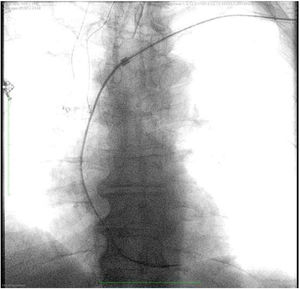

Monitorización intraoperatoriaEs recomendable realizar las extracciones mediante láser en un quirófano de cirugía cardíaca bajo anestesia general. El paciente debería estar preparado en caso de necesitar una esternotomía o toracotomía de urgencia, incluyendo monitorización invasiva de la arterial radial y colocación de un catéter venoso central (fig. 1). Asimismo, un equipo de circulación extracorpórea y perfusionista debe hallarse disponible en el quirófano.